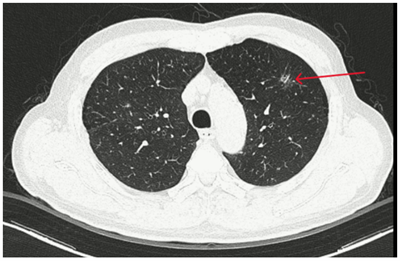

Case lâm sàng: Ứng dụng trí tuệ nhân tạo (Artificial intelligence – AI) trong chẩn đoán và điều trị sớm Ung thư phổi tại Trung tâm Y học hạt nhân và Ung bướu, Bệnh viện Bạch Mai

Case lâm sàng: Ứng dụng trí tuệ nhân tạo (Artificial intelligence – AI) trong chẩn đoán và điều trị sớm Ung thư phổi tại Trung tâm Y học hạt nhân và...

Theo GLOBOCAN 2022, ung thư phổi đứng đầu về số ca mới mắc (2.480.301 ca mới mắc chiểm 12.4%) và dẫn đầu số ca tử vong (1.817.172 ca tử vong chiếm 18.7%) trên toàn thế giới.  Tại Việt Nam tỷ lệ mắc...